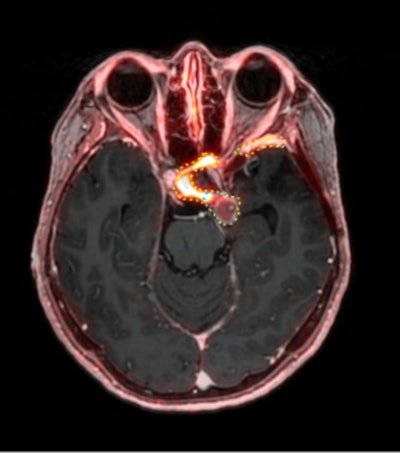

A 53-year-old patient (patient number four) with a recurrent pituitary adenoma with extension of a cystic component of disease to the medial temporal lobe apparent on MRI (contoured in blue), and extension of disease to the left sphenoid bone and orbital apex apparent on [68Ga]Ga-DOTA-TATE (contoured in yellow).A 53-year-old patient (patient number four) with a recurrent pituitary adenoma with extension of a cystic component of disease to the medial temporal lobe apparent on MRI (contoured in blue), and extension of disease to the left sphenoid bone and orbital apex apparent on [68Ga]Ga-DOTA-TATE (contoured in yellow).Clinical and Translational Radiation OncologyAccording to the analysis, the median MRI volume for each physician ranged from 4.41 to 7.19 cm3, while the median PET volume for each physician ranged from 5.94 to 15.54 cm3. There was excellent interrater reliability, with an intraclass correlation coefficient of 0.95 for PET and 0.98 for MRI.

Average PET volumes were both larger and smaller than average MRI volumes for different patients. The range of differences between average MRI and PET volumes was −3.81 cm3 to +4.34 cm3. Lastly, there was a median absolute difference between average PET and average MRI volume of 2.24 cm3, which corresponds to a median relative percent difference of 20.3%, according to the authors.